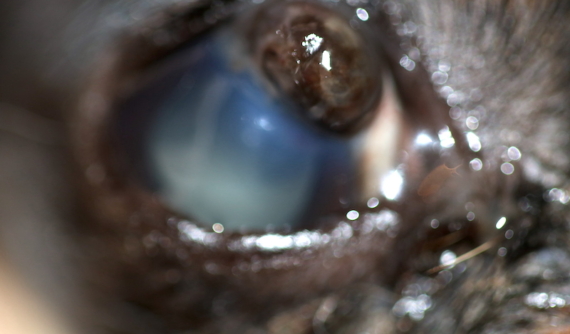

En la consulta pudimos apreciar que el arañazo era profundo y le había causado una perforación corneal, llegando a tocar hasta el cristalino y el iris. Parte del iris estaba fuera de su lugar (prolapso de iris), y salía por el hueco que había dejado el arañazo.

Las perforaciones corneales se consideran una urgencia oftalmológica. Es muy importante controlar las infecciones intraoculares y el dolor que provocan este tipo de traumatismos.

Las complicaciones más frecuentes son cicatrices con opacidad corneal, infecciones, cataratas y glaucomas secundarios.